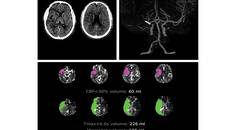

Artificial Intelligence in Clinical Neurology: Opportunities, Limitations, and the Path Forward

Aysha Jadran, MD; Saqib A. Chaudhry, MDAysha Jadran, MD; Saqib A. Chaudhry, MD - Stroke